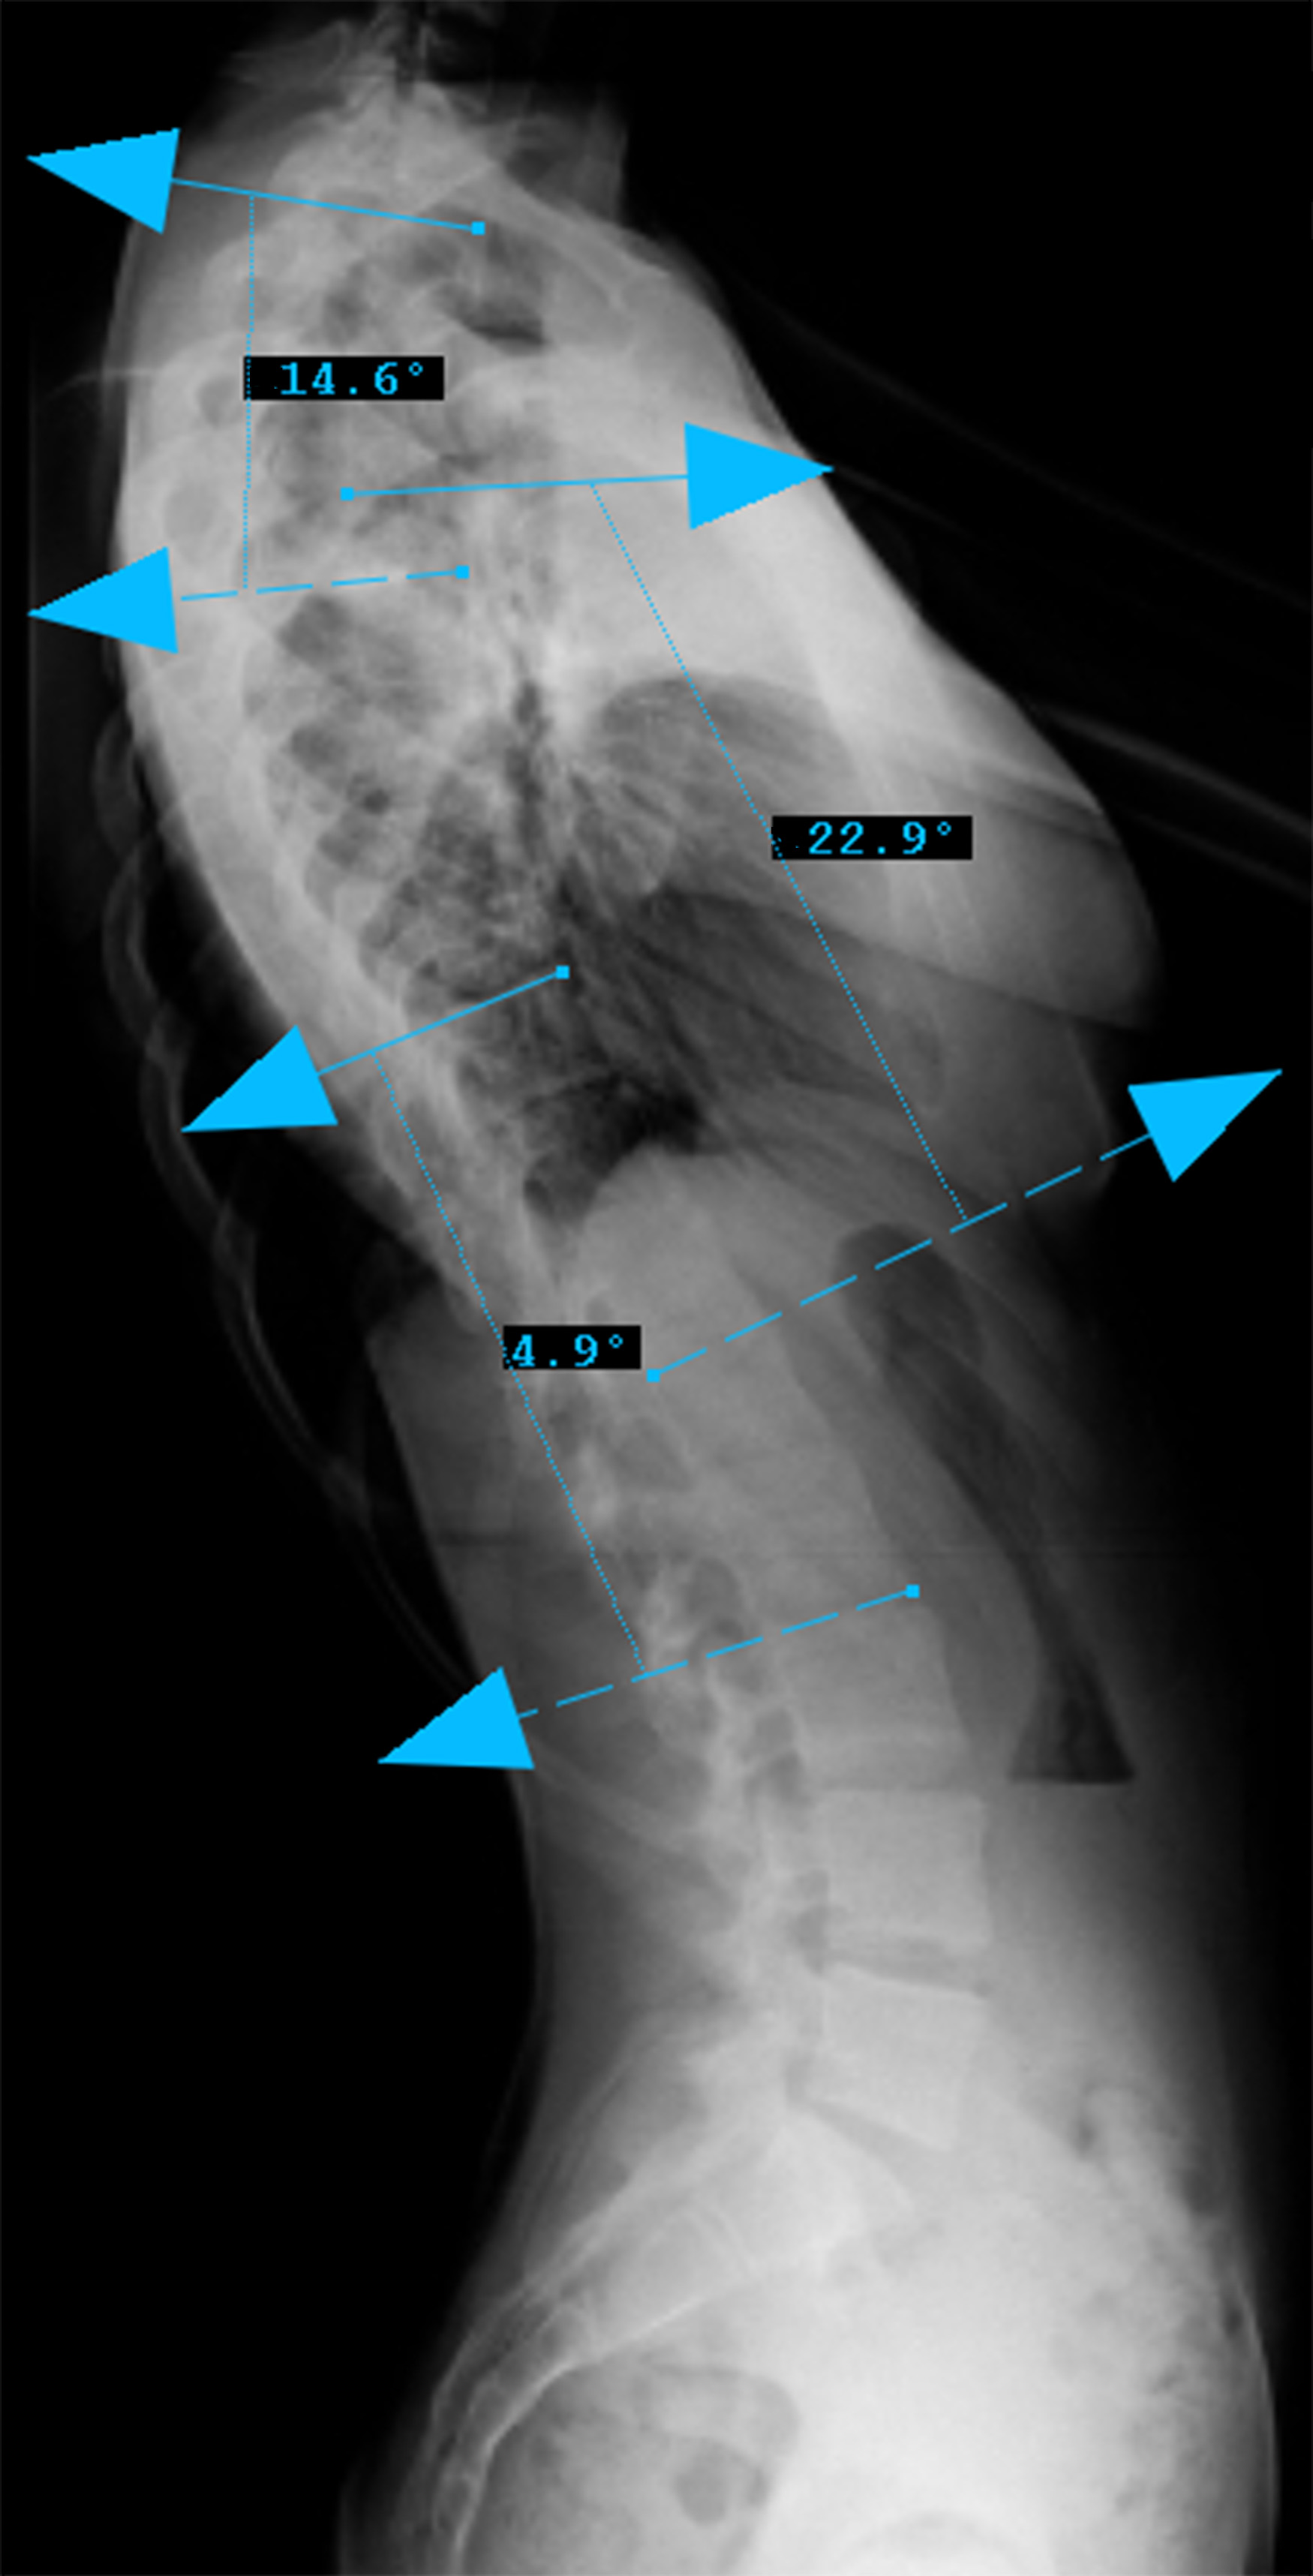

Preop LAT View